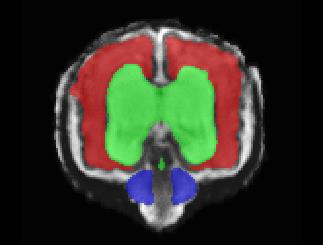

Limiting failures of machine learning systems is of paramount importance for safety-critical applications. In order to improve the robustness of machine learning systems, Distributionally Robust Optimization (DRO) has been proposed as a generalization of Empirical Risk Minimization (ERM). However, its use in deep learning has been severely restricted due to the relative inefficiency of the optimizers available for DRO in comparison to the wide-spread variants of Stochastic Gradient Descent (SGD) optimizers for ERM. We propose SGD with hardness weighted sampling, a principled and efficient optimization method for DRO in machine learning that is particularly suited in the context of deep learning. Similar to a hard example mining strategy in practice, the proposed algorithm is straightforward to implement and computationally as efficient as SGD-based optimizers used for deep learning, requiring minimal overhead computation. In contrast to typical ad hoc hard mining approaches, we prove the convergence of our DRO algorithm for over-parameterized deep learning networks with ReLU activation and a finite number of layers and parameters. Our experiments on fetal brain 3D MRI segmentation and brain tumor segmentation in MRI demonstrate the feasibility and the usefulness of our approach. Using our hardness weighted sampling for training a state-of-the-art deep learning pipeline leads to improved robustness to anatomical variabilities in automatic fetal brain 3D MRI segmentation using deep learning and to improved robustness to the image protocol variations in brain tumor segmentation. Our code is available at https://github.com/LucasFidon/HardnessWeightedSampler.